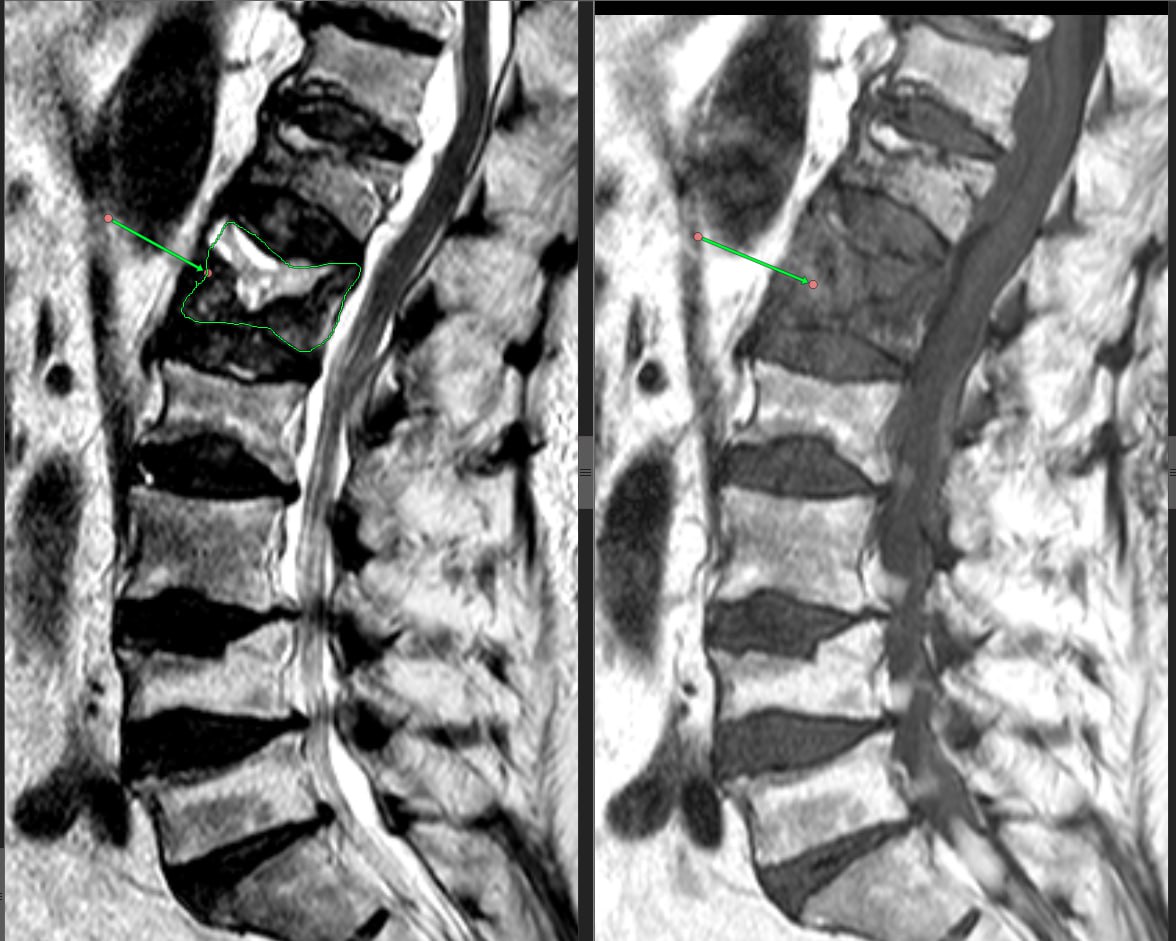

На фото - пример перелома на фоне остеопороза.